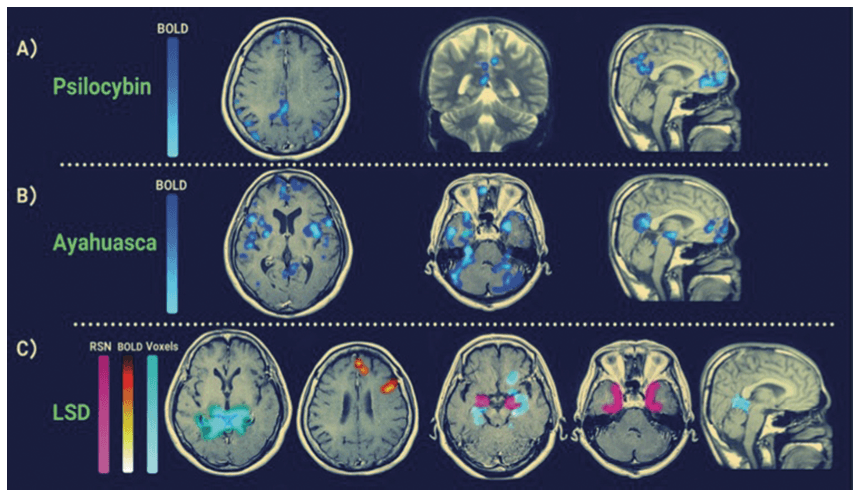

A total of 17 psilocybin studies were assessed, twelve using fMRI (2 of 12 using 7 Tesla fMRI, remaining using 3 Tesla) and two using Electroencephalogram (EEG) or Magnetoencephalogram (MEG). The average age of subjects across these studies was 34.6 years with a standard deviation (SD) of 8.8 years. The average number of participants across the studies was 26 with a SD of 19. Out of the 17 studies, 13 had a placebo control group. Four Ayahuasca studies were assessed, with all four using fMRI (two using 1.5 Tesla and two, 3 Tesla). The average age of subjects across these studies was 35 years with a SD of 17.8 years, and the average number of participants was 28 with a SD of 5.9 years. Only one of these studies had a placebo control group. Eight LSD studies were assessed, with seven using (3 Tesla) fMRI, one using EEG and one using MEG. The average age across these studies was 29.6 years with a SD of 2.8, and the average number of participants was 20, and the SD was 6.4 participants. All studies had a placebo control group. No published research papers assessing how mescaline and DMT modulates the DMN in humans were found. Table 2 is a summary of the findings and study characteristics for the research articles included in this systematic review. Figure 3 shows the specific DMN brain regions detected via fMRI that are modulated by psychedelics.